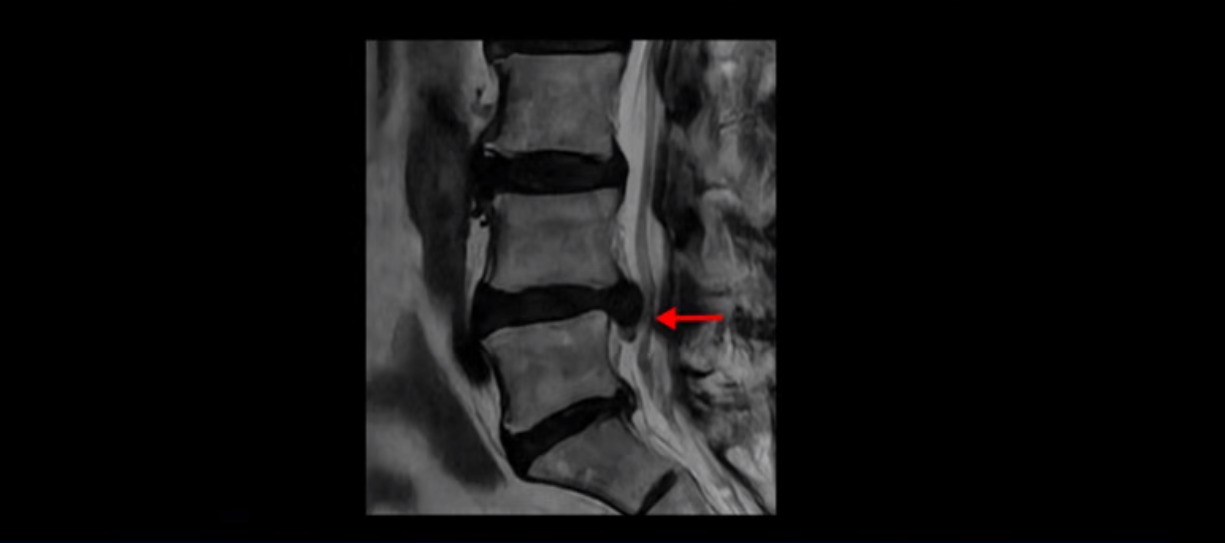

걸을 수 있는 거리는 점점 짧아지고 왼쪽 발의 근육이 빠져서 신발이 헐거워졌다는 얘기 들으셨죠? 이분 MRI를 보면

디스크 파열은 심해 보이나 신경 구멍이 좁아지는 협착증으로 보자면 저희 다른 치료 후기에 나오시는 협착증 환자분들의 MRI에 비해 신경 구멍은 넓은 편입니다. 그래서 신경이 정말 심하게 눌릴 때 나타나는 다리의 힘 빠짐 증상은 없었고 통증, 즉 아프다는 증상을 제일 심하게 호소하셨습니다.